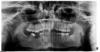

omik Опубликовано 19 июля, 2012 Поделиться Опубликовано 19 июля, 2012 Два года назад мне сделали панорамный снимок и врач сказал, что мне надо бы удалить зуб мудрости слева вверху. Он практически горизонтально растет и упирается в соседний зуб. Снимок приложен. У меня 3 зуба мудрости - 2 не видно на поверхности, 3-й - на поверхности, недавно лечила его от кариеса. Они меня особо не беспокоят. Иногда немного зудят и чешутся, но не сильно. Недавно случайно нашла интернете информацию, что зубы мудрости необходимо удалять обязательно чуть ли не у всех. Что они скорее всего все равно когда-нибудь воспалятся и тогда уже удалять больнее. Прочитала пару историй на этом форуме - удалять теперь мне страшно - столько осложнений бывает. Вопрос: надо ли удалять 8-ки в моем случае? Спасибо, заранее, за ответ. Ссылка на комментарий

Bier Опубликовано 19 июля, 2012 Поделиться Опубликовано 19 июля, 2012 38 наверное стоит удалить, а вот с 28 я бы может и не спешил. Займитесь протезированием, уже есть большие проблемы. Ссылка на комментарий

omik Опубликовано 19 июля, 2012 Автор Поделиться Опубликовано 19 июля, 2012 Спасибо всем за ответы. Значит, стоит запастись мужеством и удалить 38 и м.б. 28. А стоит ли удалять зуб мудрости справа вверху? Он достаточно большой и вроде не мешает остальным зубам. Действительно, ем я в основном одной стороной. Нижний 6-й зуб мне удалили лет в 12-ть. Сейчас уже не представляю, почему не смогли его вылечит??( Верхний зуб над удаленным как-бы подался вперед. Если ставить имплант вместо удаленного зуба, можно ли не удалять верхний? Сколько надо будет поставить имплантов - один или два? Мне 2 года назад терапевт сказала, что там такое большое пустое место, что возможно надо будет ставить 2 импланта. Хотя это как-то странно... Спасибо еще раз за ваше мнение. Ссылка на комментарий

Bier Опубликовано 19 июля, 2012 Поделиться Опубликовано 19 июля, 2012 там без ортодонта никак, надо выправлять заваленную 7ку, возможно действительно 2 имплантата вместо 6го, ну и внедрять и спиливать верхний 6й зуб. 1 Ссылка на комментарий

Bier Опубликовано 3 августа, 2012 Поделиться Опубликовано 3 августа, 2012 будет нарушение окклюзионной плоскости, блокируещее нормальные жевательные движения, что приведет в последствии к проблемам с суставом.Из-за наклоненного 7го зуба между 7м зубом и имплантатом будет ретенционный пункт для остатков пищи, что может привести к периимплантатиту и пародонтиту. Ссылка на комментарий